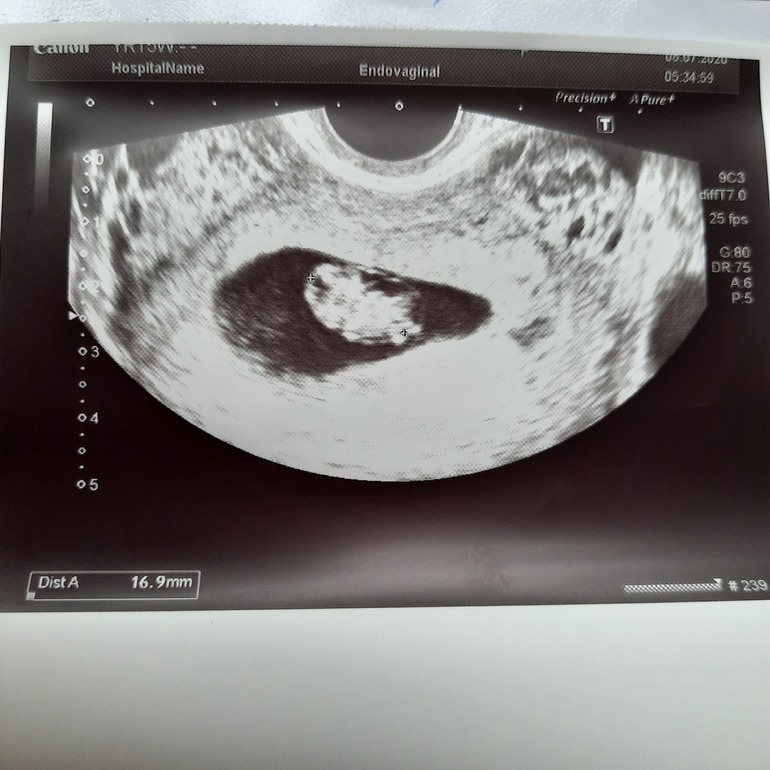

Приветик знатоки!!! Знаю что рано но погадайте мне кого же мы ждём?

😂😂😂 знаете в сообществе зачатие гадают по тестам , начиная с 5-6дпо, теперь тут мы будем гадать мальчик/девочка по узи на 10 неделе🤪

Хочу одинаково и дочку и сына. Просто ооочень хочеться узнать пораньше. Спасибо всем за предположения и гадания Через пару неделек сообщу кто же там живёт 🥰

Узнали кого ждем🌸 Посмотрим кто в домике сидит ?